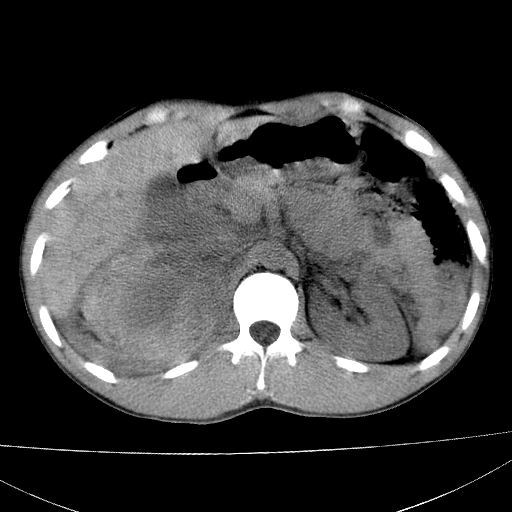

标题: CT15860:男,21岁,腹部外伤2小时伴胸疼。 [打印本页]

标题: CT15860:男,21岁,腹部外伤2小时伴胸疼。

肝脏及肾脏明显有损伤性改变并激发腹腔内积液(血),以肝脏撕裂及肾周积血显著。

1)肝破裂伴腹腔积液(血)。2)右肾破裂伴右肾包膜下及肾周血肿。3)腹部空腔脏器穿孔可能。4)右侧少量胸腔积液(血)。

肝肾挫裂伤,右肾周及包膜下血肿,腹腔积液,不排除空腔脏器穿孔,建议行增强检查

肝肾挫裂伤,右肾周及包膜下血肿,腹腔积液

肝、右肾包膜下血肿,右侧腰大肌及腹膜后血肿;腹腔少量积血;腹腔疑有少量游离气体伴肠破裂。

1肝挫伤伴腹腔积液。2右肾挫裂伤伴右肾包膜及肾后间隙肿血肿。3右肾脏周围的积气,十二指肠显示结构不清,考虑十二指肠降部破裂可能性大。